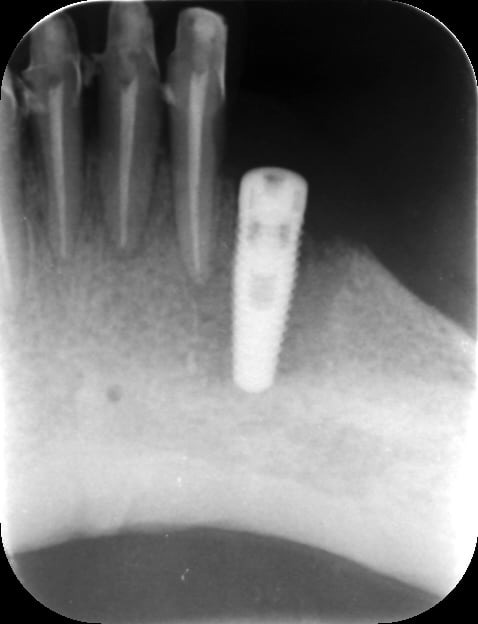

J'ai posé il y a 3 semaines 2 implants NOBEL REPLACE TAPERED en site de 33-44 pour stabilisation PAP inf.

Le patient s'est plaint de douleur importante en position de 33. Cette douleur a été suivie d'un abcès traité par ATB.

Aujourd'hui je prends une radio (la première à 1 semaine ne montrait rien) et je m'aperçois que j'ai eu une fonte osseuse due sans doute à un échauffement pendant la pose.

Que feriez vous ?

1°) Wait and see.

2°) Dépose et repose dans 2 mois ?

Dépose 5 minutes montre en main... Il était totalement fibro pas intégré.

Perte osseuse ++, je réévalue à 3 mois...